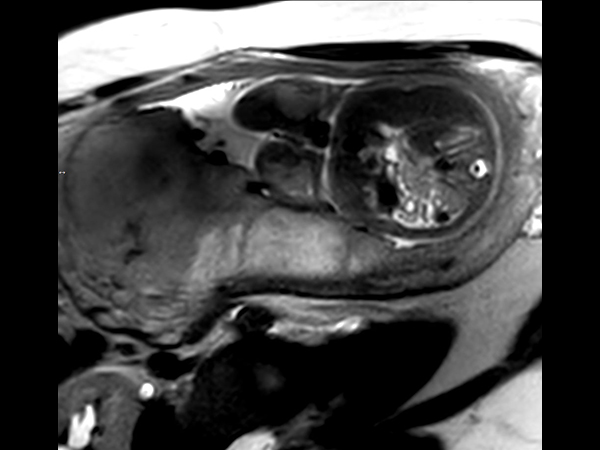

Pregnant patient, referred to MRI for fetal brain and spine imaging.

Axial T2w TSE single shotCompressed SENSE